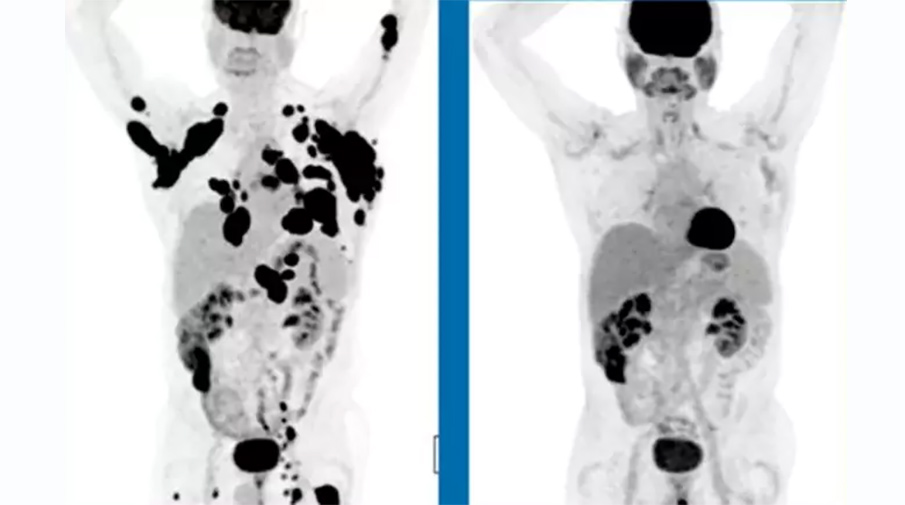

62-летний человек с диагностированной неходжкинской лимфомой в декабре 2015 года и спустя 3 месяца после приема препарата

В исследовании принимал участие 101 пациент с тремя различными формами лимфом, причем в тяжелой, терминальной стадии заболевания, когда никакие способы лечения уже не действовали. В отчете говорится, что у трети таких пациентов спустя шесть месяцев наблюдалась полная ремиссия —

это означает, что спустя полгода в их организме исчезли все признаки заболевания.

При этом у восьми из 10 пациентов опухоли за указанный период сократились как минимум вдвое. «Эти результаты выдающиеся и показывают, что более чем треть пациентов с агрессивной формой неходжкинской лимфомы потенциально могут быть излечимы после одного принятия препарата», — говорится в сообщении компании.